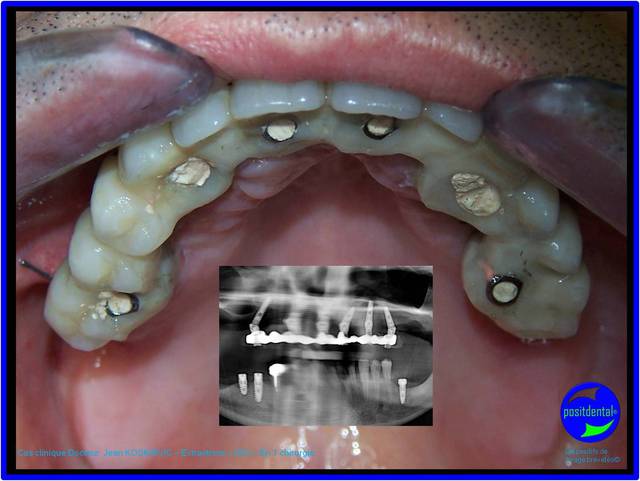

projet prothétique réhabilitation complète implanto porté en MCI, la S.I.A.O permet d'objectivé la faisabilité

-prothèse métallique présent lors du scanner

-mobilité trop importante pour prendre une empreinte du maxillaire

Résultat clinique de la MCI en 1 temps chirurgical

La photo est prise à 24h de l'intervention la pano à 2 mois